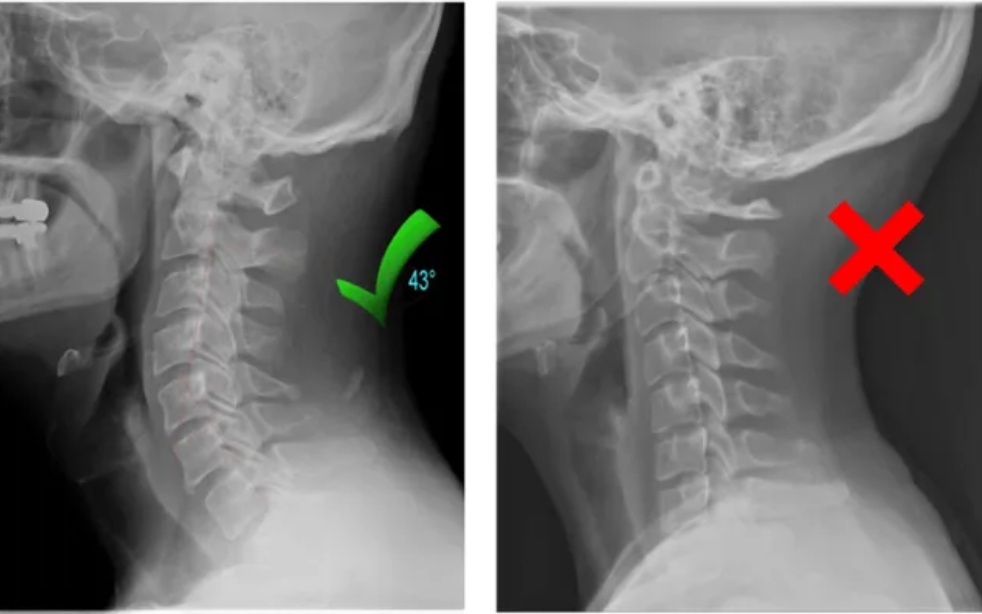

2. Votre cou a perdu sa courbure naturelle.

Des années passées le nez collé à son téléphone, à travailler à un bureau et à adopter une mauvaise posture pendant le sommeil peuvent aplatir la courbure naturelle de la nuque.

Cela entraîne un affaissement des vertèbres cervicales, une compression des nerfs et l'apparition de douleurs chroniques qu'aucun massage ni oreiller ne peut véritablement soulager.

✓ Restaurer la courbure naturelle de votre cou